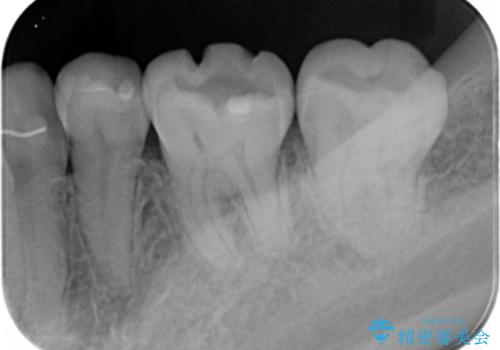

e-maxインレー治療

- 過去に治療した銀の詰め物が取れて来院された患者様です。

詰め物のやりかえをするのなら白い詰め物でやりかえたいとのことなのでe-maxインレーでの治療を行いました。